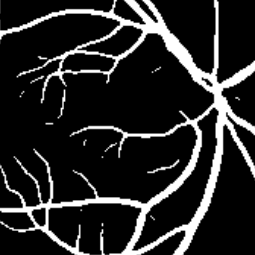

Semantic segmentation of blood vessels is an important task in medical image analysis, but its progress is often hindered by the scarcity of large annotated datasets and the poor generalization of models across different imaging modalities. A key aspect is the tendency of Convolutional Neural Networks (CNNs) to learn texture-based features, which limits their performance when applied to new domains with different visual characteristics. We hypothesize that leveraging geometric priors of vessel shapes, such as their tubular and branching nature, can lead to more robust and data-efficient models. To investigate this, we introduce VessShape, a methodology for generating large-scale 2D synthetic datasets designed to instill a shape bias in segmentation models. VessShape images contain procedurally generated tubular geometries combined with a wide variety of foreground and background textures, encouraging models to learn shape cues rather than textures. We demonstrate that a model pre-trained on VessShape images achieves strong few-shot segmentation performance on two real-world datasets from different domains, requiring only four to ten samples for fine-tuning. Furthermore, the model exhibits notable zero-shot capabilities, effectively segmenting vessels in unseen domains without any target-specific training. Our results indicate that pre-training with a strong shape bias can be an effective strategy to overcome data scarcity and improve model generalization in blood vessel segmentation.